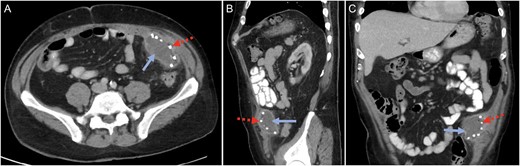

His blood tests showed a white cell count of 18.9 × 109/L with neutrophils of 8.7 × 109/L and lymphocytes of 7.4 × 109/L. The renal function was normal but liver function tests were mildly deranged: ALT 222 U/L, AST 118 U/L, GGT 175 U/L, ALP 247 U/L and bilirubin of 20 μmol/L. The C-reactive protein was 150 mg/L. The patient underwent a computer tomography (CT) scan of his abdomen and pelvis which showed a 6 cm × 7.5 cm × 2.5 cm collection consistent with an abscess underlying the anterior abdominal wall in the region of left iliac fossa (Fig. 1). This in close proximity to the mesh used in his previous hernia repair that was performed earlier. There was evidence of uncomplicated sigmoid diverticular disease.

Computed tomography (CT) scan in the (A) cross-sectional, (B) sagittal and (C) coronal planes confirming a mesh-related abscess in the left iliac fossa. Solid blue arrow marks the abscess. Broken red arrow marks the metallic tack that was used to secure the intraperitoneal mesh.